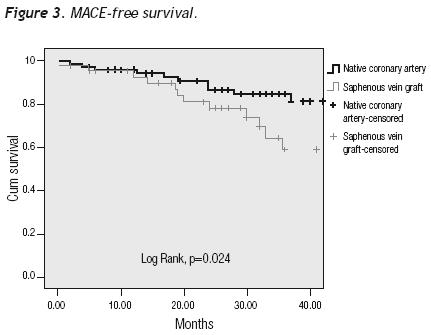

A tendency towards a lower MACE incidence was observed in group 2 at 3 years (34.6% vs. 23.0%, p = 0.075). The use of bare–metal stents or DES did not modify the incidence of accumulated MACE. The MACE–free survival by the Kaplan–Meier analysis was 65.0% in the SVG group and 89.1% in the native vessels group (p = 0.024). TVR–free survival was 74.8% and 92.8%, respectively (p = 0.022; Figures 3 and 4). Risk estimation for TVR with the use of DES revealed a reducing–effect tendency, with OR 0.28 (IC 95%, 0.06–1.31, p = 0.09). The TVR–free survival at 36 months in the whole population with the use of DES was 94.1%, compared to 89.8% with bare metal stents (p = 0.64).

In our study, the MACE–free and TVR–free survival at 36 months was higher in the PCI of native vessels group than in the PCI of venous grafts group. The use of DES did not modify the TRV rate during the 3 years of follow–up in the population as a whole.

In this study, we compare the results of intervening venous grafts versus native arteries in patients with previous coronary artery bypass surgery. Results show a higher MACE rate during the in–hospital phase for group 1 (venous grafts), and a better MACE–free and TVR–free survival for native vessel PCI. To get definite conclusions, it will be necessary to perform a randomized prospective study using distal embolic protection devices, as well as direct stenting and DES in both groups.